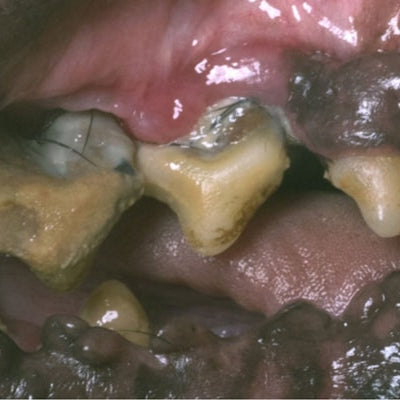

Napredni paradontitis

Če bolezen napreduje povzroči postopno propadanje obzobnih tkiv. Zobni žepi so globoki, hranjenje je oteženo, prisoten je nenehno slab zadah. Zobje so zaradi odmika dlesni navidezno precej podaljšani, majejo se in nazadnje lahko izpadejo.

Pred začetkom zdravljenja z OralClean+Care, vidi se zobni kamen in vnete dlesni.